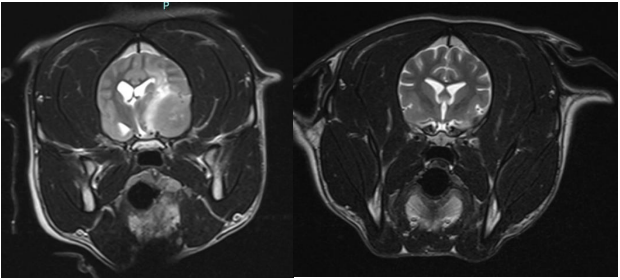

After finishing her treatment, Purdey returned home on medication and strict rest, but her progress was promising. The real miracle came three months later, when a repeat MRI scan revealed a remarkable result: Purdey’s brain tumour had completely vanished.

MRI scans of Purdey's brain before and after treatment.